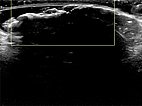

In der Sonographie (B-Bild) findet sich durch den hohen Bindegewebsanteil an der Oberfläche des Nävus direkt eine totale Schallreflexion mit einem ausgeprägten Schallschatten. Die Läsion selbst ist nicht darstellbar.

In der farbkodierten Duplexsonographie (FKDS) zeigt sich ebenfalls die totale Schallreflexion. Auch bei sehr empfindlicher Einstellung für Blutfluss (6 cm/s) keinerlei Perfusion feststellbar.